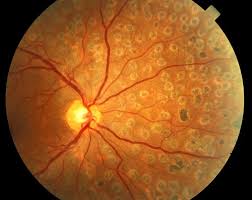

Dry ARMD;In dry age-related macular degeneration, small white or yellowish deposits, called drusen, form on the retina, beneath the macula, causing it to deteriorate or degenerate over time.

Dry ARMD